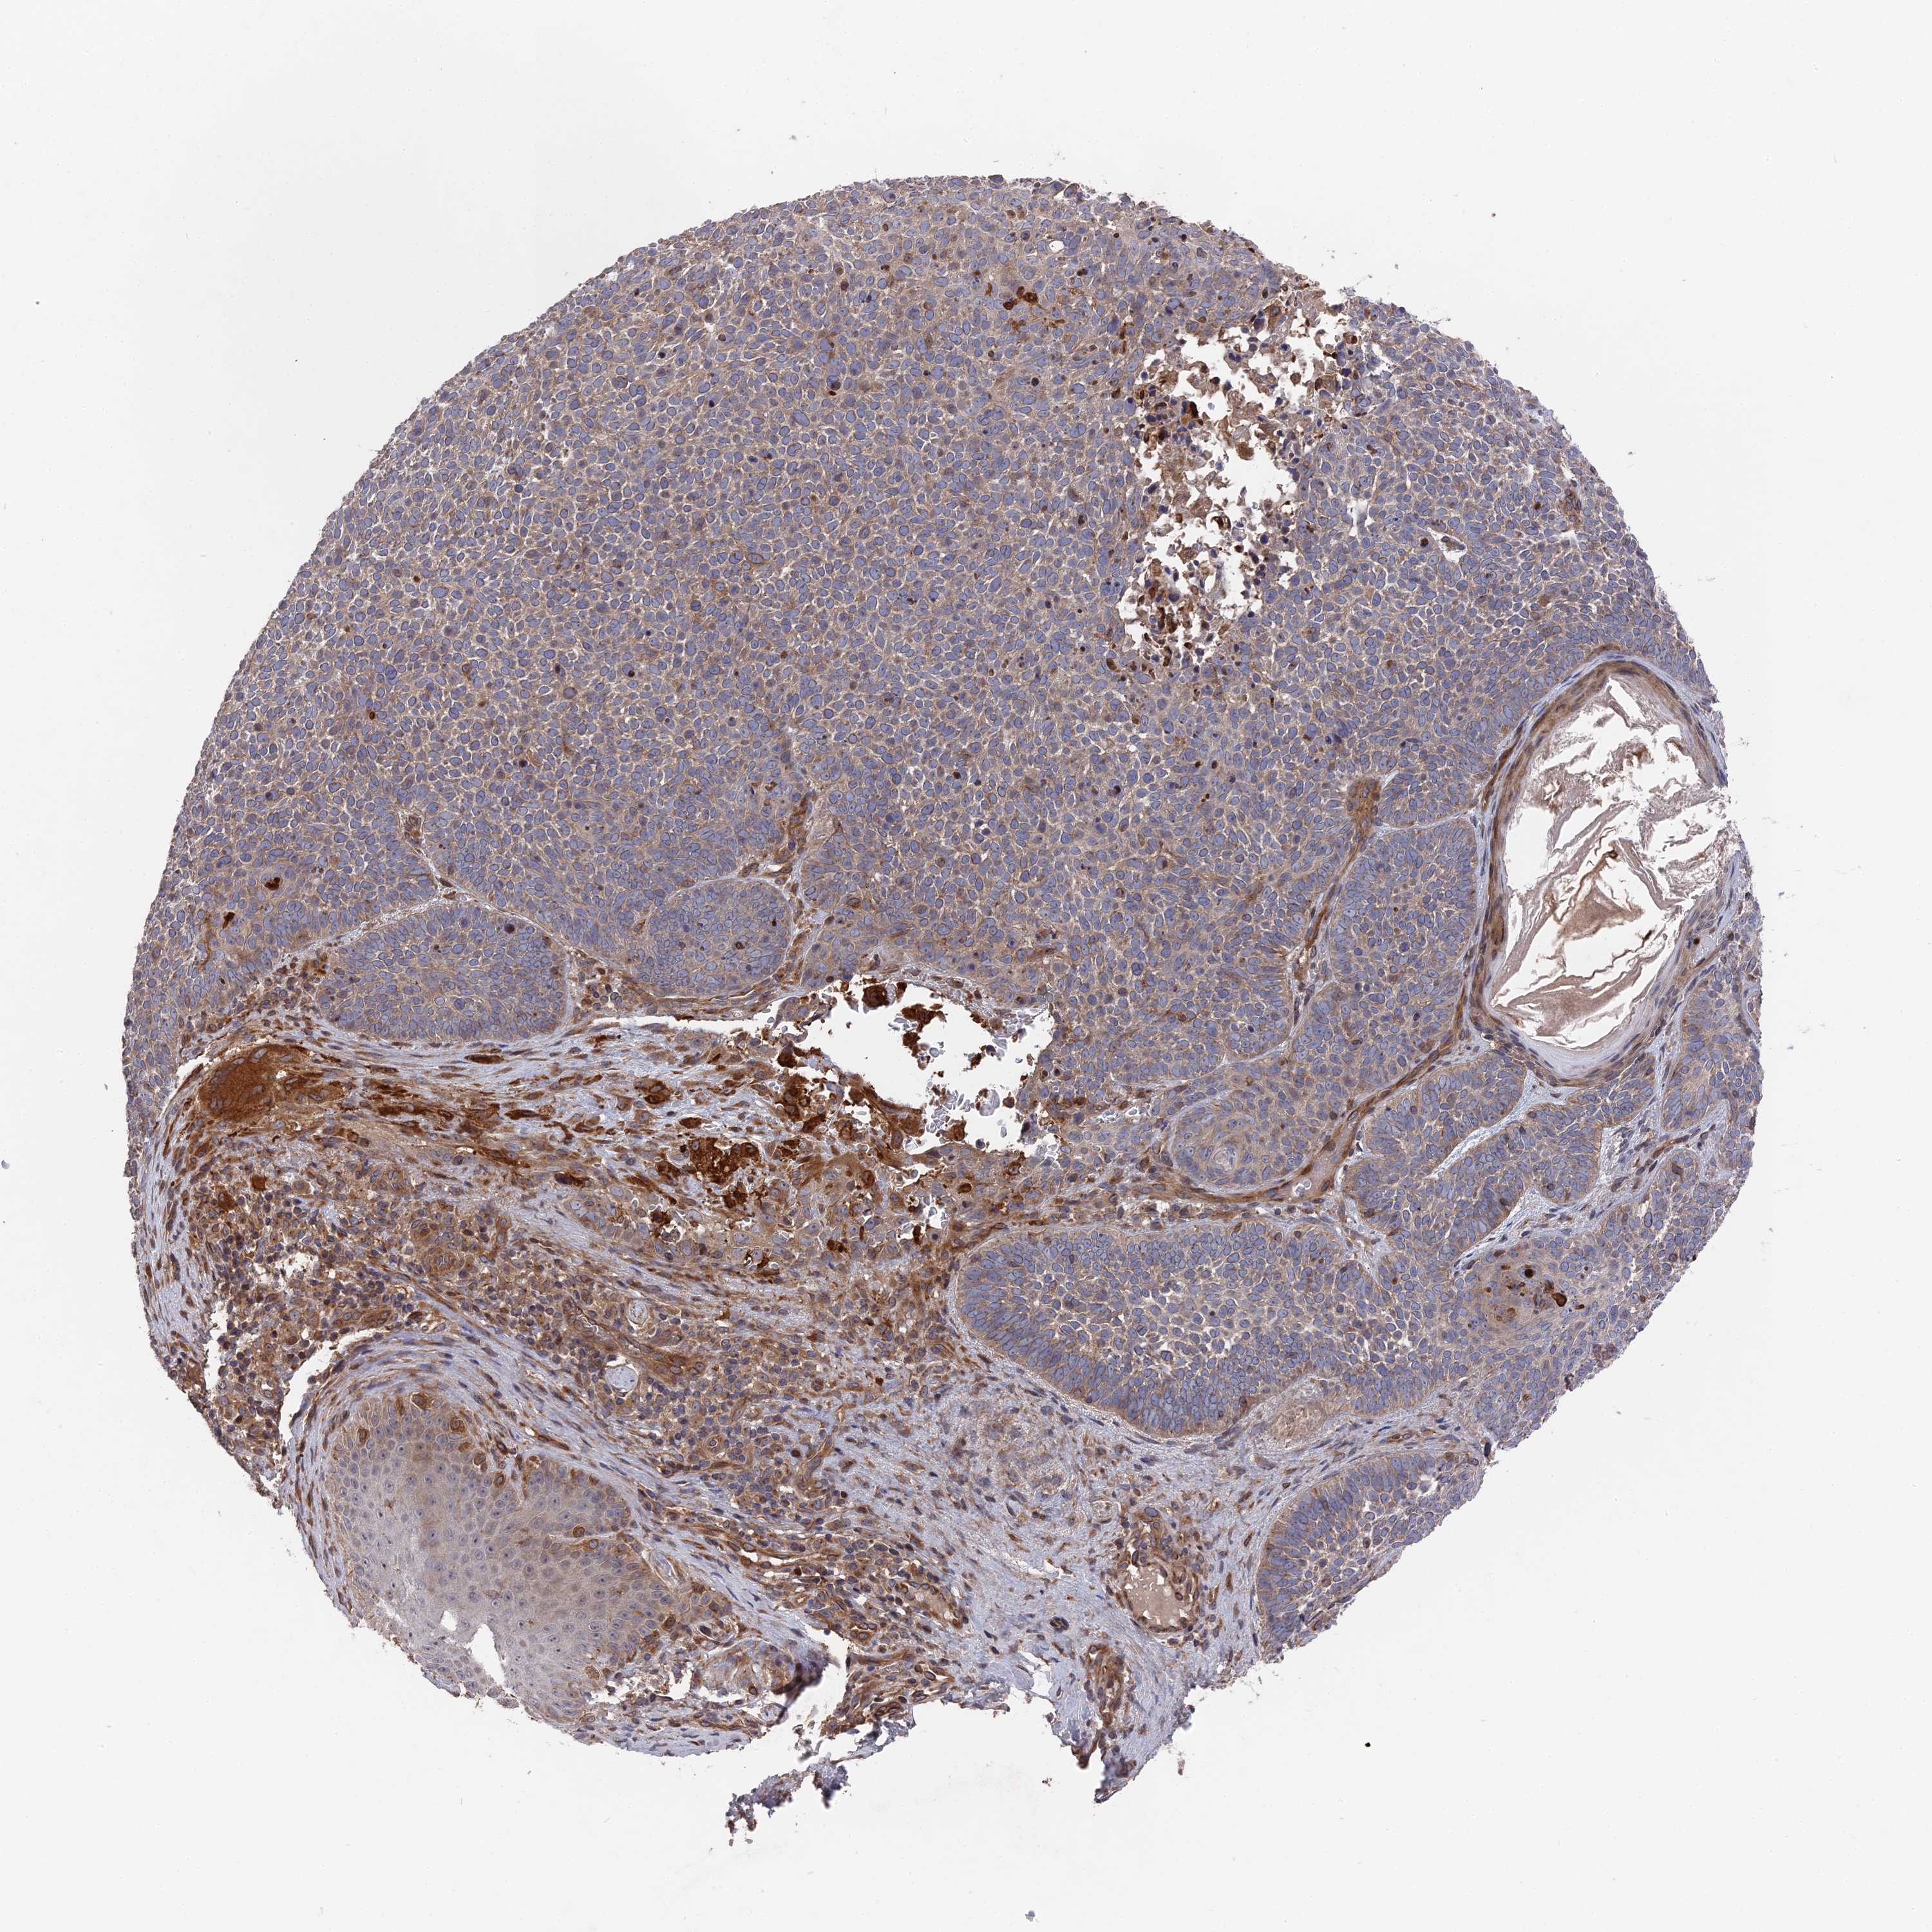

SKIN CANCER - Protein expressioni

A mouse-over function shows sample information and annotation data. Click on an image to view it in a full screen mode. Samples can be filtered based on level of antibody staining by selecting one or several of the following categories: high, medium, low and not detected. The assay and annotation is described here.

Antibody stainingi

Antibody staining in the annotated cell types in the current human tissue is reported as not detected, low, medium, or high, based on conventional immunohistochemistry profiling in selected tissues. This score is based on the combination of the staining intensity and fraction of stained cells.

Each image is clickable and will lead to virtual microscopy that enables deeper exploration of all samples and also displays staining intensity scores, fraction scores and subcellular localization as well as patient and tissue information for each sample.

Antibody HPA041745

Staining

High

Medium

Low

Not detected

Intensity

Strong

Moderate

Weak

Negative

Quantity

>75%

75%-25%

<25%

None

Location

Nuclear

Cytoplasmic/membranous

Cytoplasmic/membranous,nuclear

Basal cell carcinoma